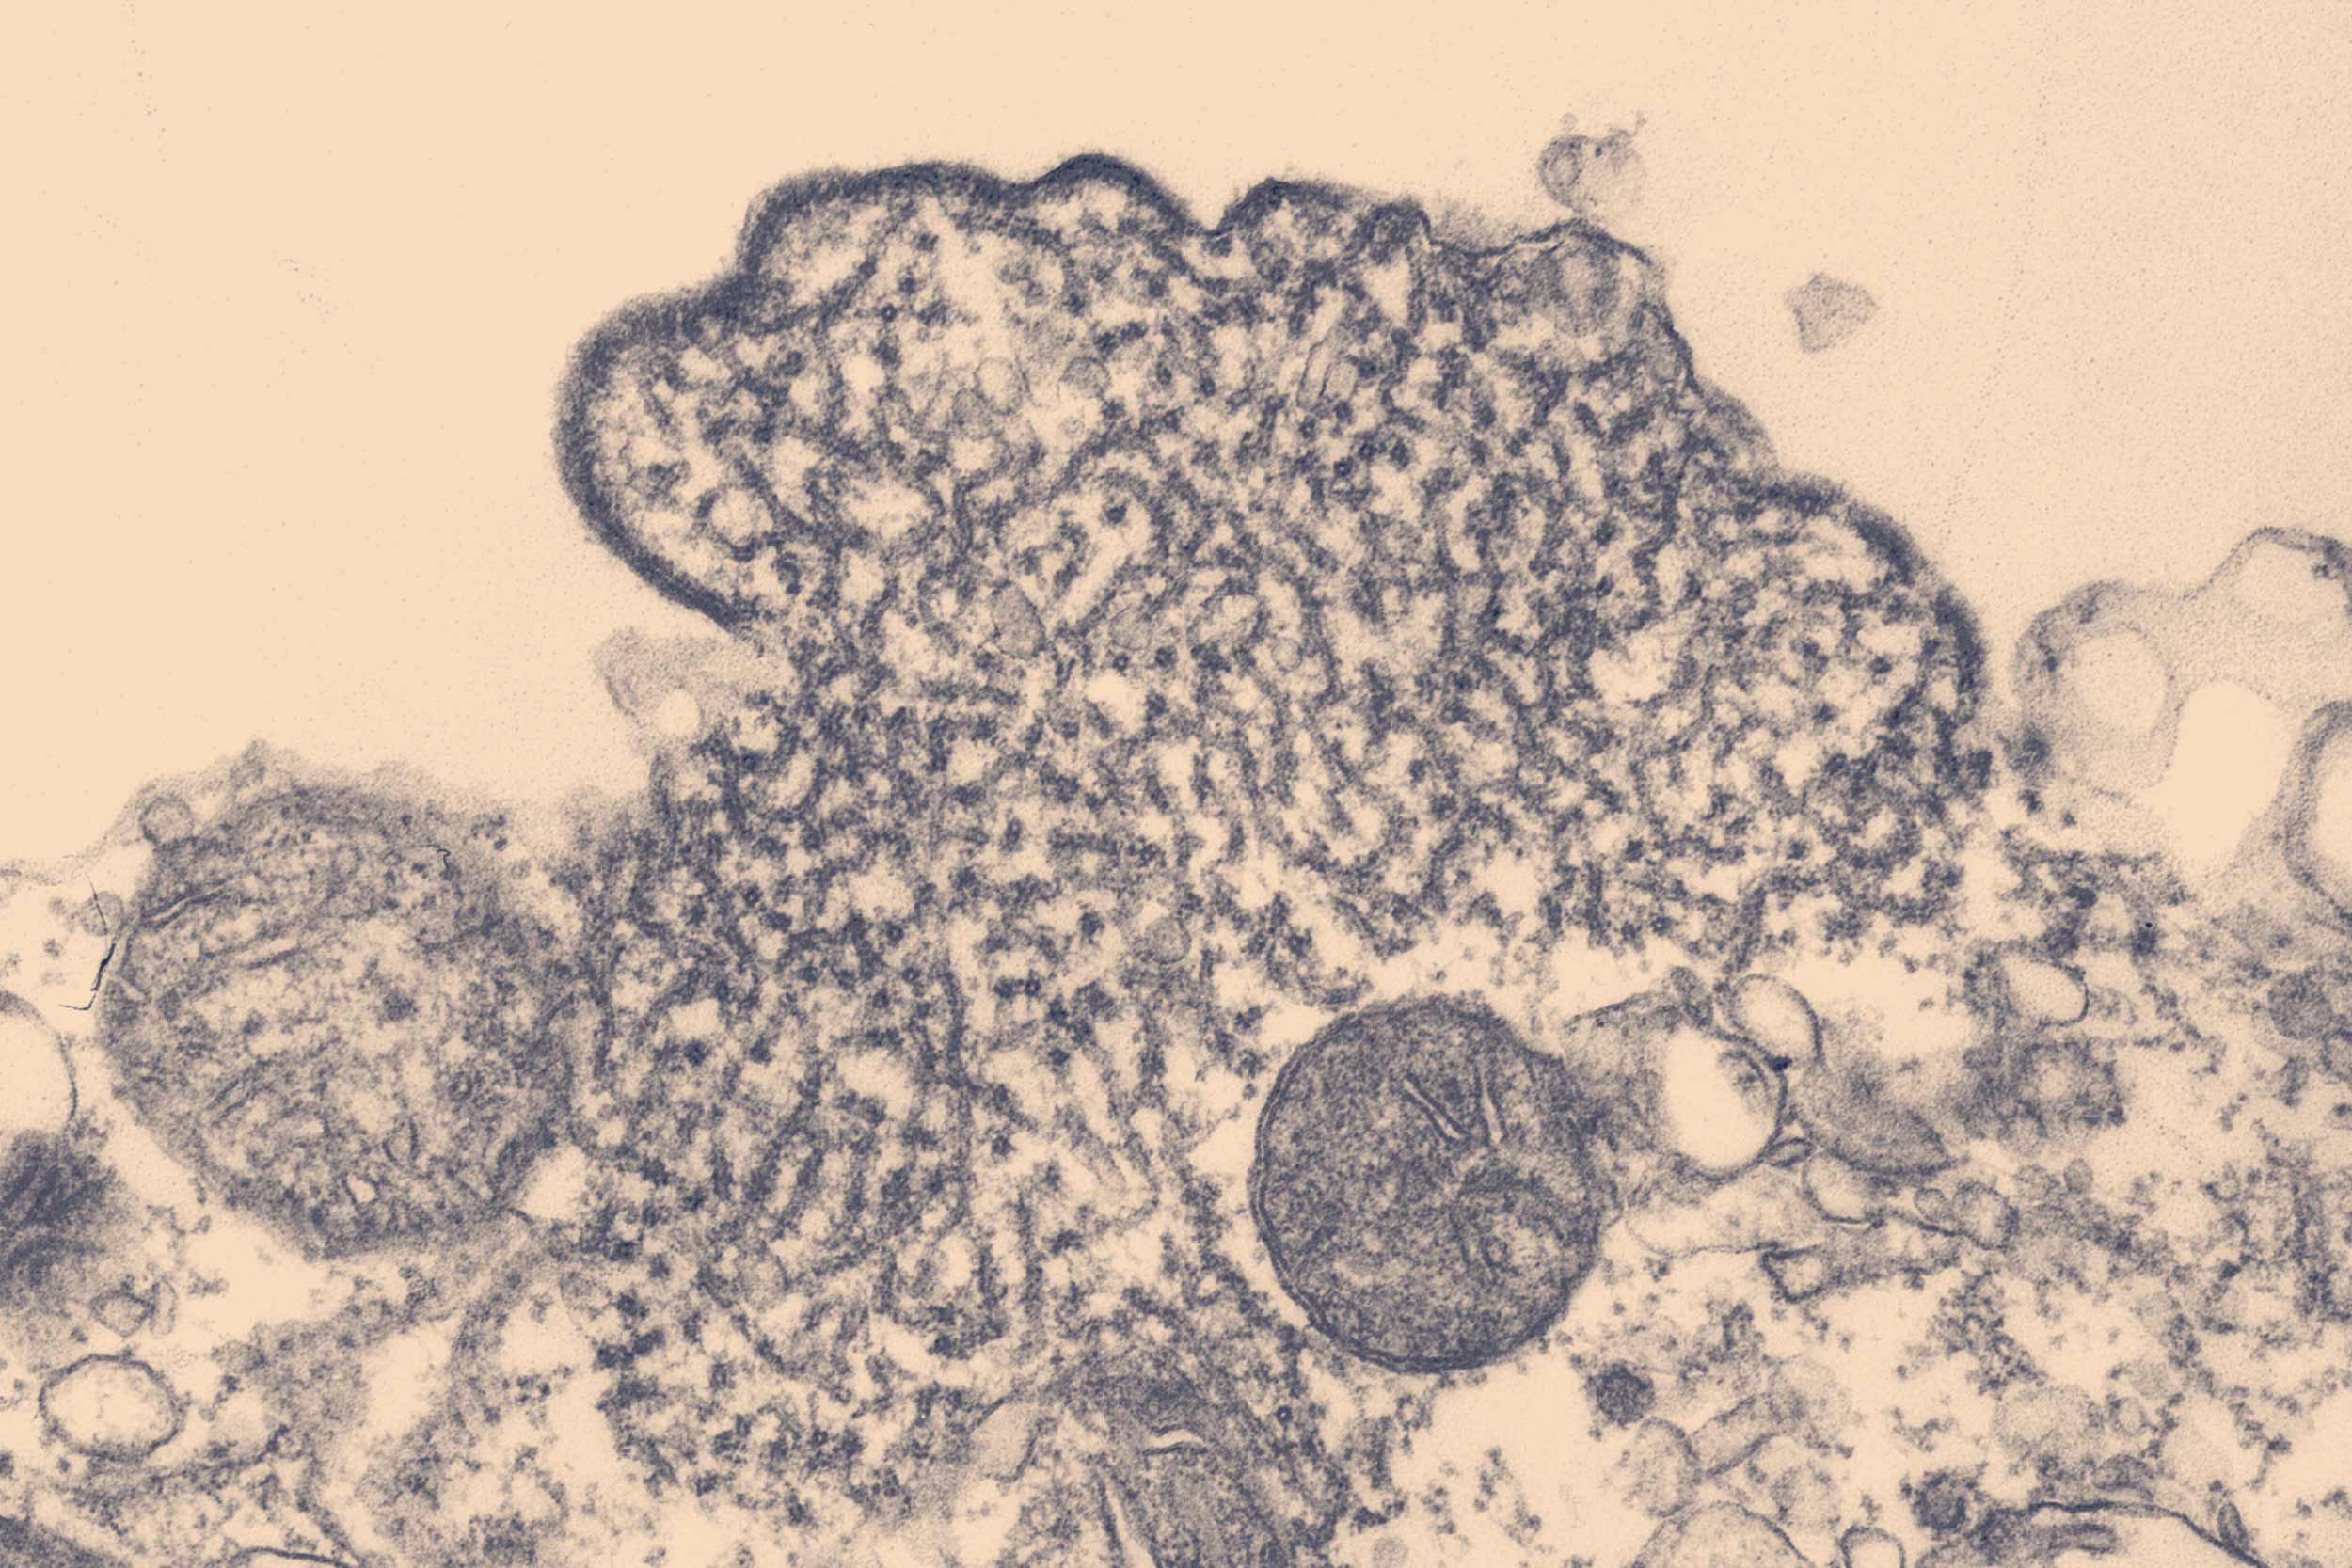

The danger of Nipah lies in its ability to infect and replicate in a variety of cells by exploiting ephrin receptors, which play a role in cell movement. Once inside the body, Nipah affects epithelial cells in the lung airways, endothelial cells lining blood vessels, and neurons, contributing to its high lethality.